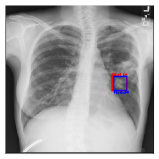

CXR8 [21] is one of the most commonly accessible radio-logical examination for many lung diseases. The data consists of 112,120 images collected by 30,805 patients. As shown in Table I, nine class labels of normal state and eight diseases including cancer are defined for classification. The data is divided into training set and test set, and the classification accuracy and ROC curve with several well-known deep network such as VGG16, GoogLeNet, and ResNet, are reported on the original paper [21]. In addition, 984 Bounding Boxes (B-Box) are provided for localization. Fig. 5 shows image examples of CXR8. The red rectangle in the image shows given B-Box.

IV-D Investigation of the generated heatmap

By using the training result of the Adaptive DBN, the heatmap images were generated in addition to detection of B-Box. The heatmaps in Fig. 10 to Fig. 14 show the detection result of B-Box and the generated heatmap for some images. The red and blue rectangles in the image are given B-Box and detected B-Box, respectively. A heatmap is represented by the continuous value of range , where the color map is jet color array (red means high value, while blue means small value). The diseases for detected B-Boxes in Fig. 10 to Fig. 14 were as follows; Infiltration (Fig. 10), Mass (Fig. 10), Nodule (Fig. 10), Mass and Pneumothorax (Fig. 10), Atelectasis (Fig. 14), Infiltration (Fig. 14), Atelectasis (Fig. 14), Atelectasis (Fig. 14).

Overall, the red area of the generated heatmap included in both the given B-Box and detected B-Box. On the other hand, the blue or yellow areas didn’t include in these B-Boxes. This tendency was seen in not only large diseases (e.g. Cardiomegaly or Infiltration) such as Fig. 10, but also small diseases (e.g. Mass or Nodule) such as Fig. 10. We consider that the experimental results caused by the discrete heatmap with binary output of final RBM layer instead of continuous heatmap. As a result, the red regions represents localization with strong relation to diseases and blue regions represents localization with weak relation. The generated heatmap shows the portion with strong relation more clearly.

In Fig. 14, the detected B-Box was located at a little upper than the given B-Box. The red area of the heatmap was also at upper position. The detected B-Box is slightly larger than the given B-Box. The detected B-Boxes are almost same as the given B-Boxes except the different size. For better detection capability, the feature of the generated heatmap will be investigated with the medical specialists.